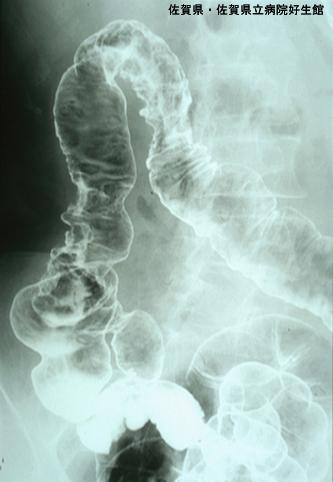

症例提示(所在地,施設名等): 佐賀県・ 佐賀県立病院好生館 (Dr.下田ら)

疾患(病理主体)の分類炎症性・潰瘍性疾患/静脈硬化性大腸炎

部位(臓器別)大腸/2区域以上の大腸にまたがるもの

検査方法X-P

病変の最大径(ミリ)40以上